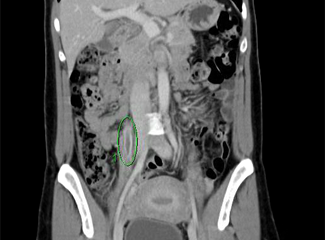

CT scans of the abdomen and pelvis (Figures 1-3) revealed bilateral ovarian vein thrombosis, worse on the right side than the left. A heparin infusion was immediately started to prevent a pulmonary embolism and therapy with broad-spectrum antibiotics (gentamicin and clindamycin) was also initiated.

Figure 3